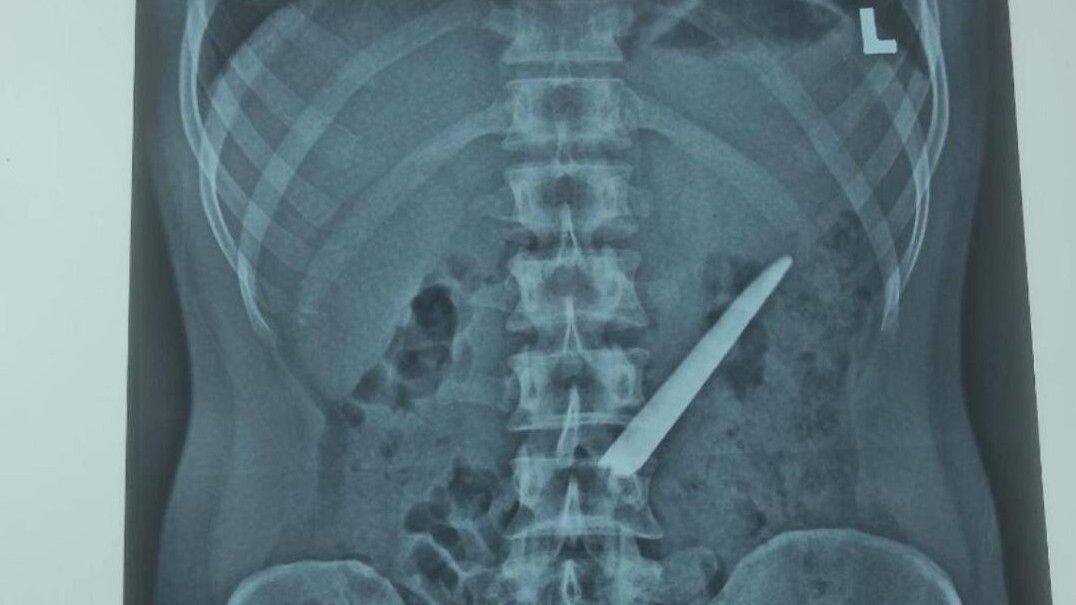

10 phút, cứu bệnh nhân sốc đa chấn thương

Y tế 24h - 15/09/2022

Tối 14/9/2022, BVĐKTƯ Cần Thơ cho biết, các bác sĩ đã cứu sống bệnh nhân nguy kịch do bị bức tường đổ đè lên người sau 10 phút cấp cứu.